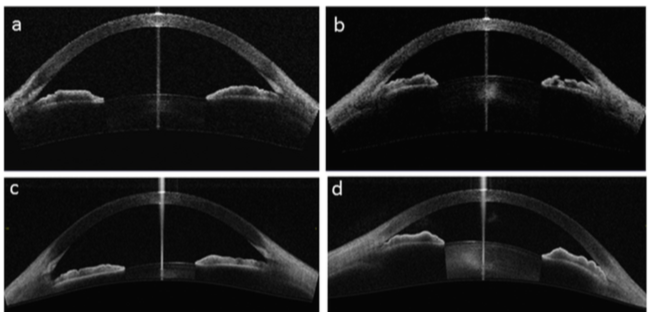

3. Evaluación Clínica de lentes intraoculares

Las imágenes de la AS OCT de la cámara anterior permiten también medir la posición dentro del ojo de una lente intraocular. En caso de lentes fáquicas de cámara posterior, la AS OCT, permite  obtener medidas preoperatorias que ayuden a la elección del diámetro de la lente a implantar, obteniendo valores de medida del A-A (ángulo-ángulo), que ayudan a la determinación del diámetro. Posteriormente al implante de la lente la AS OCT ayuda a la obtención del Vault (espacio entre la lente y el cristalino), valor importante en el seguimiento de estas lentes.